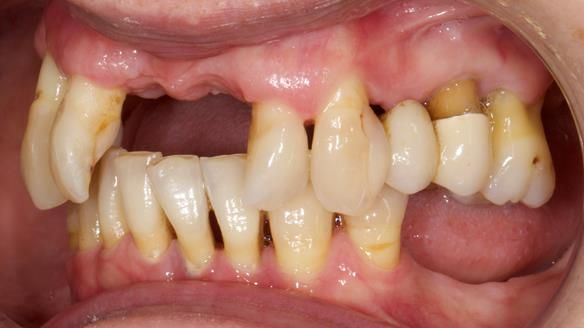

She had previously suffered from generalised periodontitis – stage IV, grade C, currently stable, with reduced attachment across the upper arch.

By the time she came to me, her periodontal condition was stable — but the aesthetics in the upper jaw were very poor.